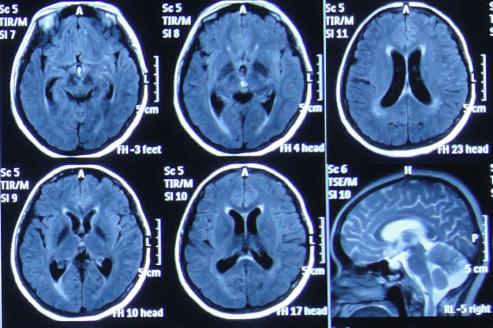

患者于2015年7月31日,无明显诱因突发头痛发热症状,体温升高至38.6℃,因自行服药3天后无改善即2015年8月3日,就诊并住入第1家的位于四川省成都市某军医院的神经内科,查头MRI示“右侧小脑半球结节影,环性强化”(图-1)。

图-1:2015年8月3日头部MRI